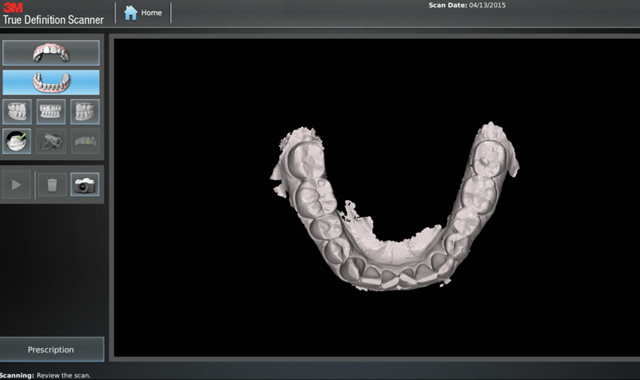

Fig. 1

to Align, and then complete the Invisalign prescription with the uploaded scans. The following case illustrates the many benefits of using the True Definition scanner with Invisalign.

We scanned the upper and lower arches capturing all incisal edges, occlusal surfaces, interproximal embrasures, distals of terminal molars and 3 mm of gingival margins (Figs. 4-7). There was no need to scan the bite. We submitted the scans to Align by completing the prescription on the True Definition scanner (Fig. 8).